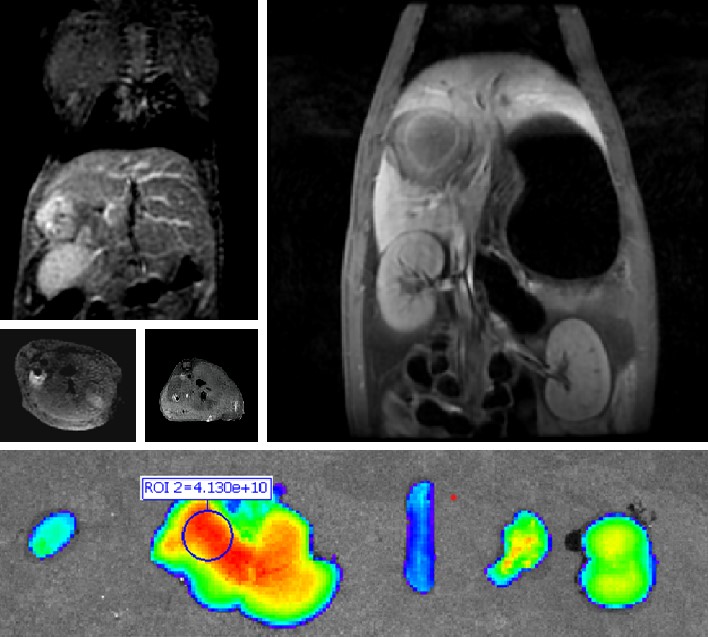

伟德国际1946官网自主研发双模态造影剂PL002,首次提出通过整合磁共振技术,弥补现有荧光染料假阳性率高、透射深度有限等的短板,进而提升手术的精确性,降低手术过程中的风险,是全球首个获批临床试验的荧光/磁共振双模态造影剂,目前也已经获得美国FDA临床试验批件。